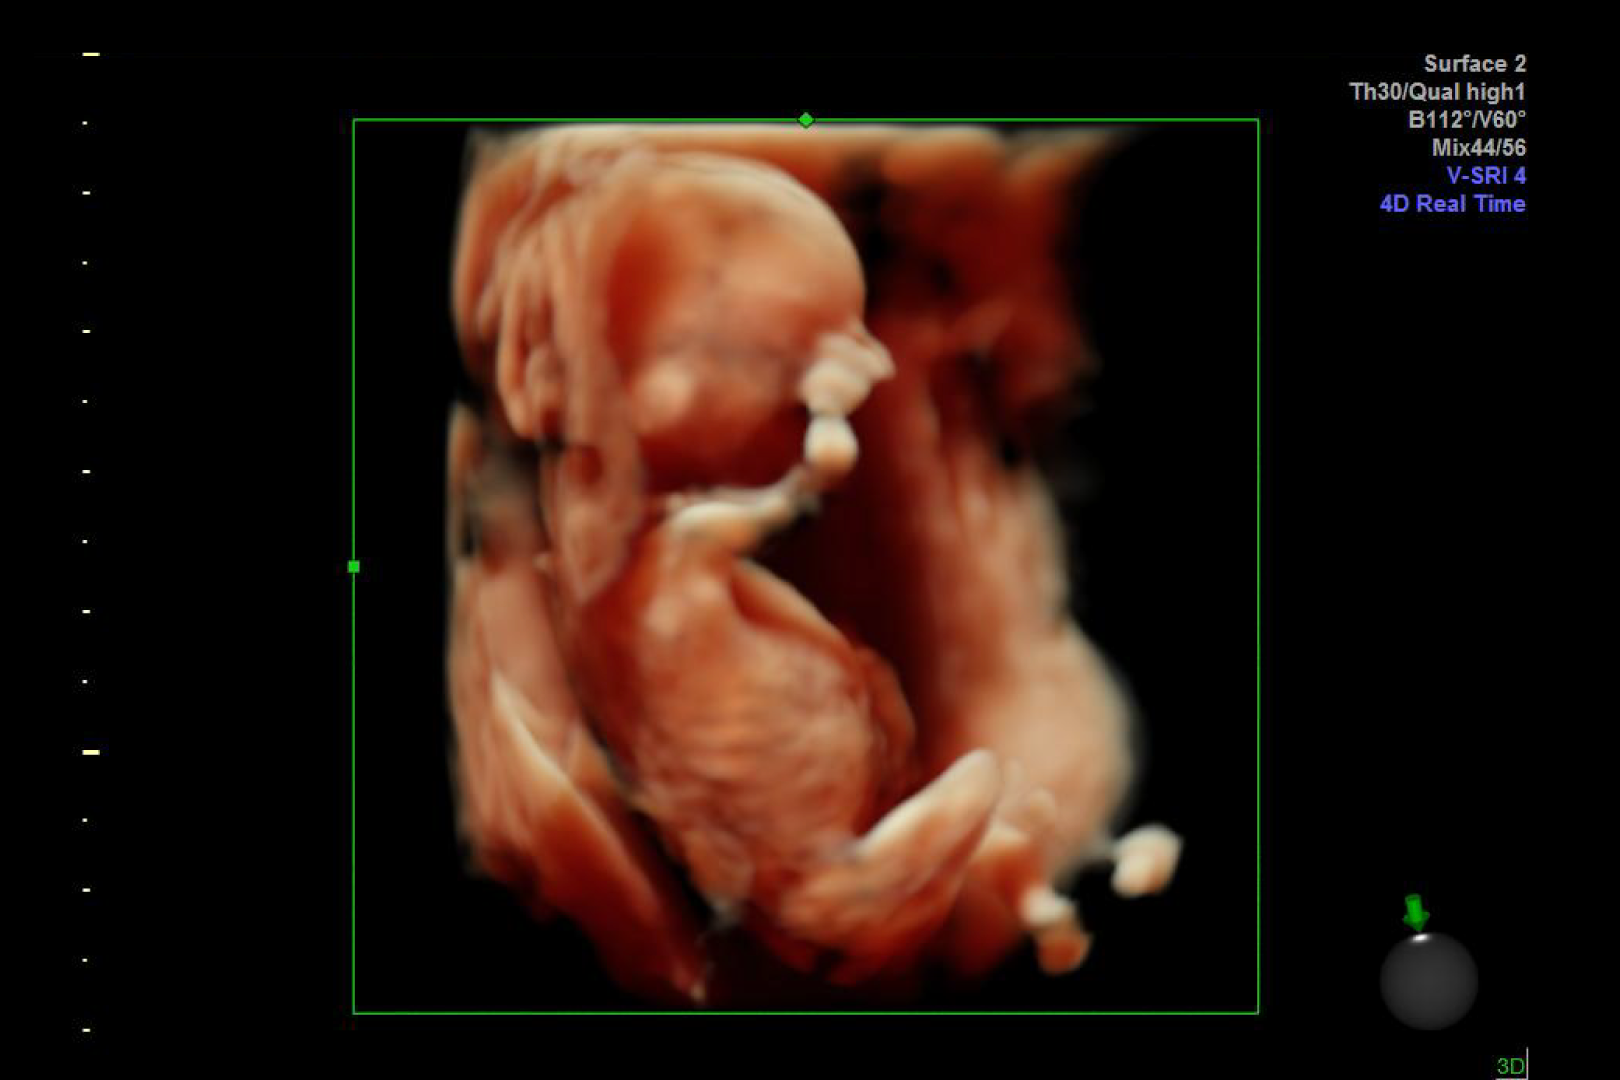

HD Live quinta dimensión, Imágenes de volumen con profundidad y claridad, que aportan un realismo anatómico para un mejor diagnóstico.